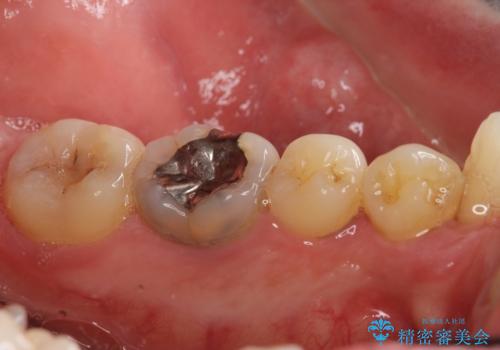

- 歯並びをきれいにしたい、歯を真っ白にしたいとのご希望により来院されました。

矯正治療とホワイトニングを提案しましたが希望されず、「接客関係の仕事で矯正治療は考えられない、短期間で治療を終わらせたい、ホワイトニングでは難しい位の人工的な白さにしたい」とのご要望により、治療前にワックスアップ模型を作製し何度もコンサルテーションを重ね、治療方針を決定しました。

歯頚ラインが変えられないことや天然歯を削るリスクをご理解頂いた上で、オールセラミッククラウンによる補綴治療を行いました。(見えない奥歯のみ天然歯のままとしました)

下の前歯1本だけ歯軸を変えるために神経をとり根管治療を行っております。

それ以外の歯は神経をとらずに済むよう、慎重かつ丁寧に歯の形態を整えました。